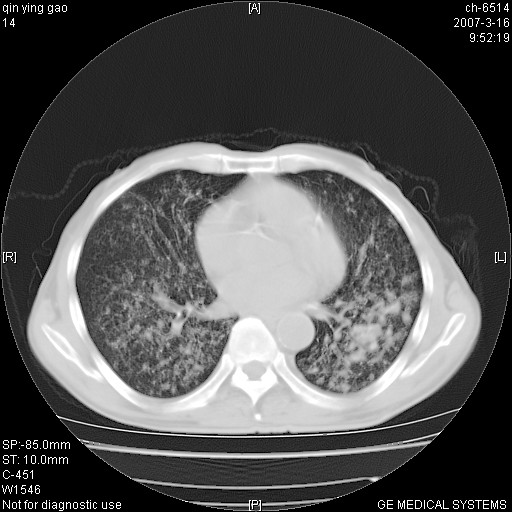

男,64岁.乏力2个月,畏寒、发热1月余。体重下降。血沉加快,白细胞不高。

双肺以中上肺野为著斑片状.结节壮密度增高影 左上肺前段可见小类圆钙化灶 纵隔淋巴结无明显肿大

双肺以中上肺野为著斑片状.结节壮密度增高影,纵隔淋巴结无明显肿大。考虑:

两肺弥漫分布的斑片状影,部分融合,左肺及纵隔淋巴结见钙化影,考虑1。tb,2。肺泡细胞癌,建议查痰检

两中上肺见有广泛分布大小不一的结节灶及斑片状影,部分融合,双下肺未见异常密度影,纵隔无明显肿大淋巴结,血沉加快,白细胞不高,首先考虑结核。 建议结合ppd检查或痰培养排除其他非特异性炎症。

中上肺野密布棉团状影,以胸膜下区为界,边缘模糊,可能是小叶或腺泡渗出及实变。全肺野弥漫分布网线样影及细小粟粒样影,可能是细支气管炎及间质内炎症。综合分析应首先考虑气道播散性感染,而肺内多处斑点性钙化,强烈提示陈旧结核复发并支气管播散。建议详细讯问病史

病变以两肺上野为著,部分病灶有钙化,纵隔窗显示病灶有新老不一,这个首先和结核脱不了干系,还有部分病灶有融洽的倾向,肿瘤也不能完全排出